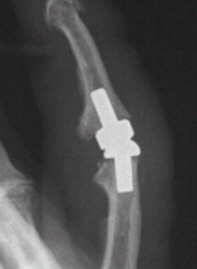

- Die Versorgung mittels einer Prothese (Kunstgelenk). Dieses Vorgehen ist nur am Fingergrund- und -mittelgelenk möglich. Dafür muss allerdings als Vorbedingung die Gelenkführung durch die Bänder intakt sein. Hierbei werden in einer ca. einstündigen Operation die abgenutzten Gelenkflächen entfernt und durch eine künstliche Prothese ersetzt. Nach der Operation ist eine intensive Behandlung mit Schienen unter Anleitung von Krankengymnasten erforderlich, die die Beweglichkeit des Gelenkes nach und nach wieder freigeben. Diese Nachbehandlung dauert etwa sechs bis acht Wochen. Eine völlig freie Beweglichkeit des Gelenks, wie bei einem gesunden Gelenk, wird hiermit nicht erreicht, jedoch Schmerzlinderung.